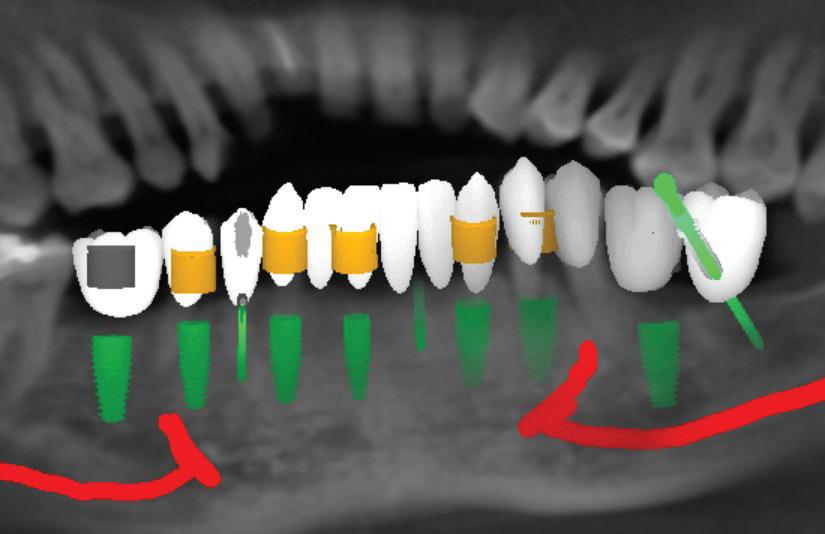

In its continuing commitment to reimagine and improve solutions for the dental industry, Carestream Dental has launched the Advance Edition of the CS 8200 3D, along with the latest updates in automated implant planning. The CS 8200 3D Advance Edition is the newest addition to the CS 8200 3D Family and builds on the success of its award-winning predecessors with extended fields of view—including two new larger FOVs—and AI-powered software that streamlines and automates the implant planning workflow.*

• AI-powered implant planning:* The enhanced implant planning module automates the implant workflow, allowing practitioners to plan implants faster and with greater precision.

Additionally, new AI-assisted software accelerates the entire implant planning process by automating time-consuming tasks. Now, preparing data for implant cases— like merging CBCT volumes with digital impressions—designing virtual crowns and digitally placing implants is all handled automatically, making implant planning faster and easier. When combined with a prosthetic-driven approach, these software updates improve treatment predictability and give doctors the confidence to deliver precise and successful implant outcomes.